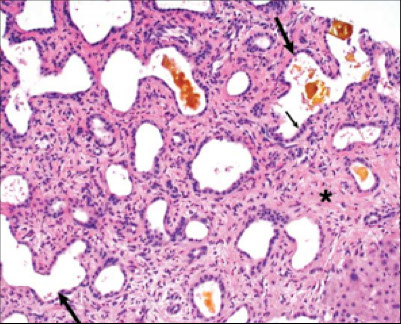

Bile Duct Hamartoma

A bile duct hamartoma is a benign tumor-like malformation of the liver. Also known as von Meyenburg complex

They are classically associated with polycystic liver disease, as may be seen in the context of polycystic kidney disease, and represent a malformation of the liver plate